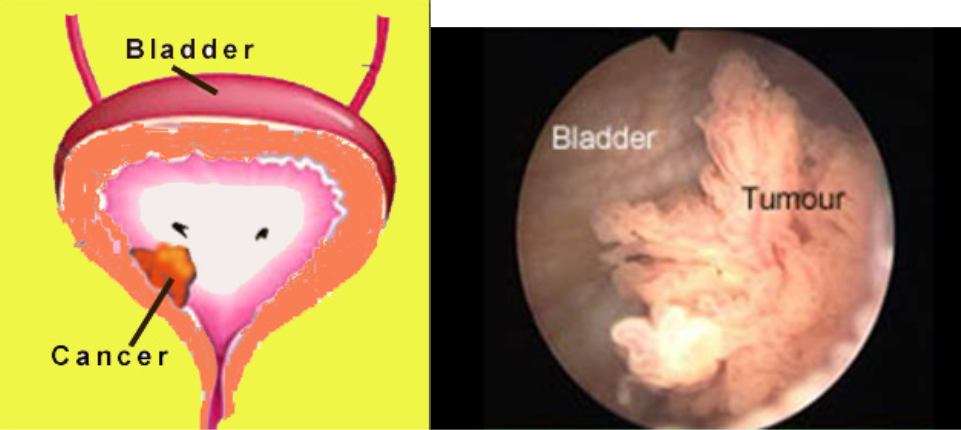

Bladder Cancer Hexvix

https://www.hexvix.com/sites/www.hexvix.com/files/images/bladder-cancer-tumor-classification-2.png

Bladder Surgery Dr Haddad Urinary Bladder Surgery Urologist

https://drhaddad.com.au/wp-content/uploads/2022/06/bladder-cancer-655x545.jpg